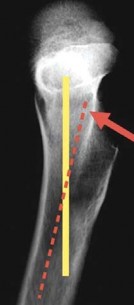

- الأشعة السينية (X-rays): هي الفحص الأول والأكثر شيوعًا. تُظهر صورًا للعظام وتُساعد في الكشف عن تضيق المسافة المفصلية، وجود نتوءات عظمية (Osteophytes)، أو أي تشوهات في بنية العظام، مما يُشير إلى تآكل المفاصل.

- الدليل الشعاعي على التآكل الشديد: تُظهر الأشعة السينية تآكلًا كبيرًا في الغضروف، وتضيق